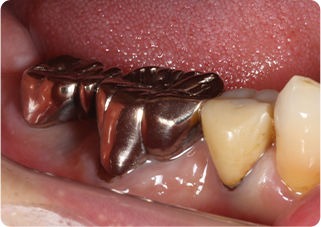

自家歯牙移植・精密根管治療・セラミッククラウン症例

術前

術後

| 主訴 | 奥歯の銀歯がぐらぐらして取れそう |

|---|---|

| 治療期間/回数 | 5ヵ月、10回 |

| 価格(税込) | 264,000円(税込) |

| リスク・副作用 | 生着不良、歯根吸収、骨性癒着の可能性 |

| ポイント | 銀歯の中でむし歯が進行し、保存不可能だったため抜歯し、後ろの親知らずを移植。移植の際に3Dプリンターで作製した親知らずのレプリカを使用し、治療時間の短縮と移植ポジションの確認を行った。生着するのを待ち、精密根管治療を行った後、セラミッククラウンを装着した。 |